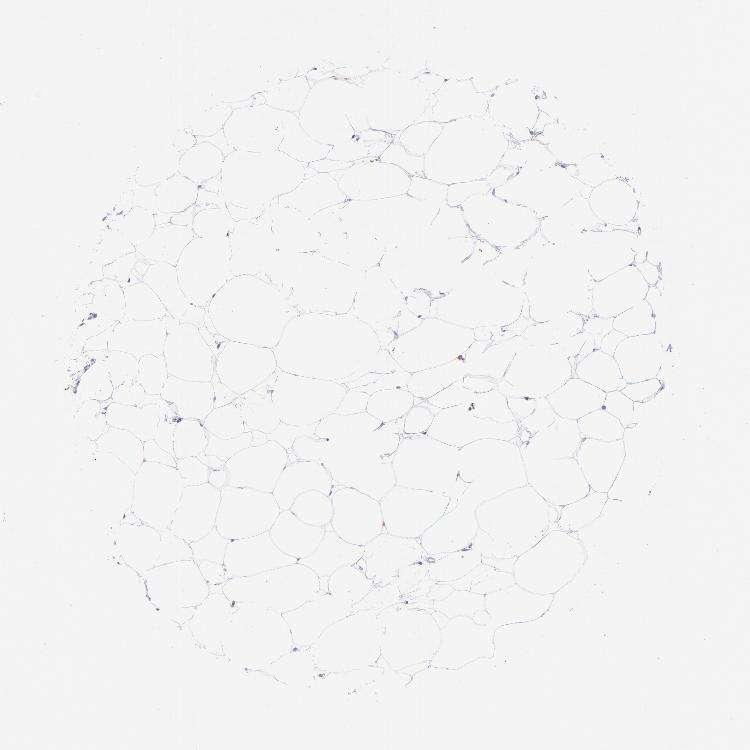

SOFT TISSUE 1 - Antibody stainingi

Antibody staining in the annotated cell types in the current human tissue is reported as not detected, low, medium, or high, based on conventional immunohistochemistry profiling in selected tissues. This score is based on the combination of the staining intensity and fraction of stained cells.

Each image is clickable and will lead to virtual microscopy that enables deeper exploration of all samples and also displays staining intensity scores, fraction scores and subcellular localization as well as patient and tissue information for each sample.

Antibody HPA014811Antibody CAB002658

Chondrocytes Not detectedNot detected

Fibroblasts Not detectedNot detected

Peripheral nerve Not detected-